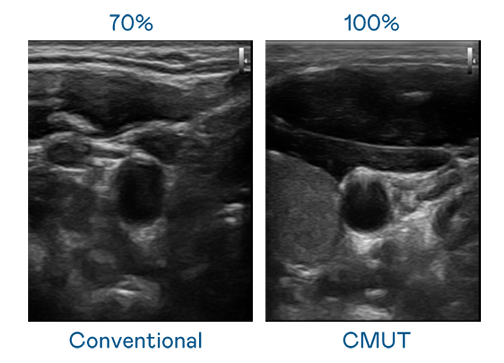

CMUT 技術是一種用電容式微機電元件來產生超音波訊號的技術。與傳統 PZT 壓電式技術相比,CMUT 頻寬增加 30%,更寬頻的超音波訊號讓影像解析度大幅提升,是實現高影像品質醫療超音波掃描、促進精準醫療發展的關鍵技術。

超音波影像的解析度高低,首先取決於探頭能發出的訊號頻寬。慈禧秘密生活国语在线观看完整免费 CMUT 可提供高清晰的超音波訊號,提供高頻寬、高靈敏度、影像紋理細節更高的超音波影像,協助醫護人員縮短影像判讀時間及利用精準的醫療影像進行診斷。